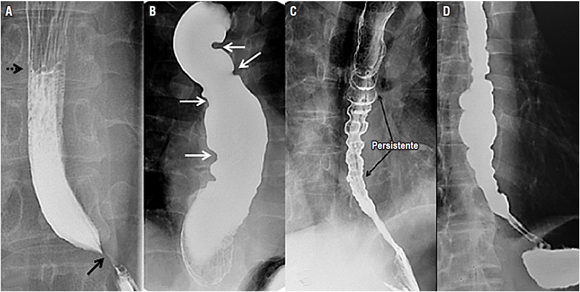

Trastornos de la motilidad esofágica

Los trastornos motores esofágicos constituyen una amplia variedad de padecimientos poco frecuentes de etiología aún desconocida. El uso del esofagograma demuestra una gran sensibilidad para el diagnóstico de una parte de los trastornos funcionales de la motilidad, pero su diagnóstico definitivo depende de los hallazgos de la manometría clásica o de alta resolución 13,14. La acalasia es una enfermedad crónica y progresiva caracterizada por una falla en la relajación del esfínter esofágico inferior, ausencia de peristalsis y aumento de la presión esofágica intraluminal 14,15 (Figura 6).

A pesar de esto, aproximadamente el 20% al 30 % de los pacientes con este diagnóstico y con hallazgos típicos radiológicos no presentan disfunción en el esfínter esofágico inferior 10,14. El espasmo esofágico difuso se presenta con contracciones no coordinadas y dolor retroesternal, y el esófago en cascanueces, con onda de propagación normal, pero con una fuerza de contracción mayor, con una duración aumentada de la contracción 14,15,16 (Figura 6). En los pacientes con espasmo esofágico difuso, las contracciones peristálticas, por su presentación intermitente, se presentan en menos del 15% de los casos 10,14.